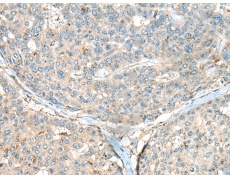

IHC positive control: |

Human gastric cancer and Human liver cancer |

IHC Recommend dilution: |

50-300 |